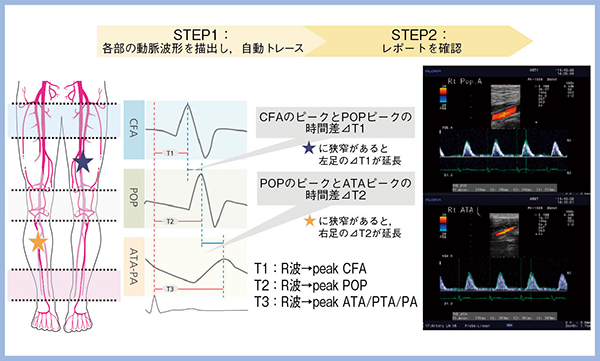

2.Transit time of Vessel Flow(TVF)

TVFは,大腿,膝窩および足部の各動脈で得られた血流波形出現時間を測定して,得られる計測値の遅延から閉塞病変や狭窄の有無と範囲を推定できる指標である。従来は,総大腿動脈(CFA)と膝窩動脈(POP)の血流のピークの時間差などを算出して評価していたが,LISENDO 880では3心拍を自動で取り込んで簡便に評価可能となった(図5)。

図5 自動TVF測定機能